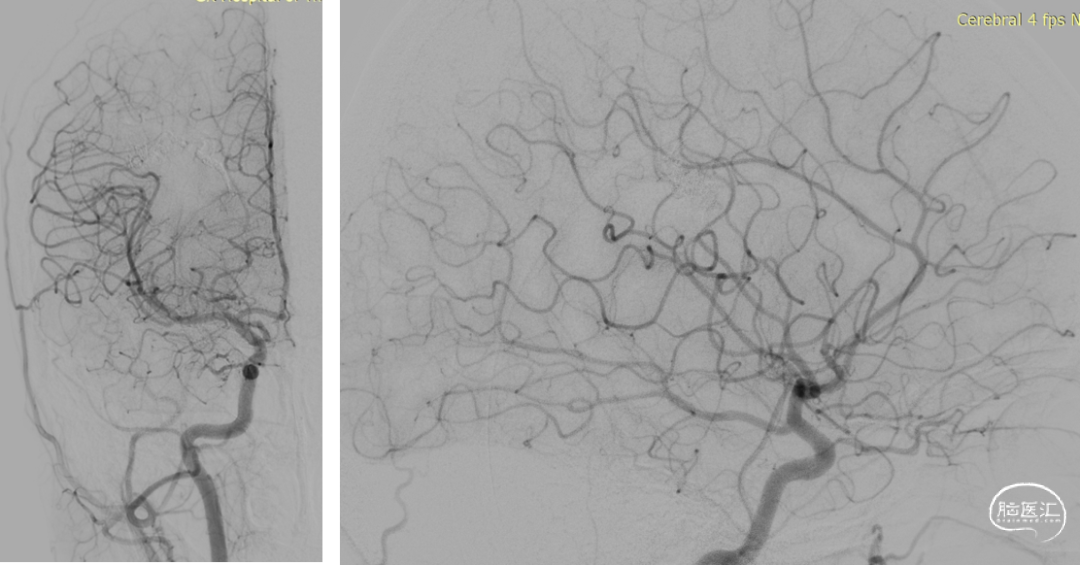

DSA:右侧额顶叶脑动静脉畸形

10个月DSA复查

静脉入路超选

供血动脉球囊保护;静脉压力锅技术,onyx18栓塞

术后即刻造影血管畸形消失

术后4个月复查DSA血管畸形无复发